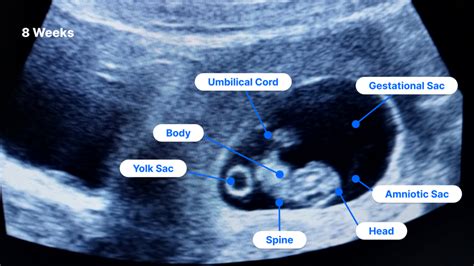

So, what exactly is a USG Fetomaternal ? Let’s clear up any confusion right away. While most pregnancies involve several routine ultrasounds – those exciting moments where you get to see your baby wiggling around – a fetomaternal ultrasound is in a league of its own. It’s not your standard, run-of-the-mill scan; it’s a highly specialized diagnostic procedure performed by a fetomaternal medicine specialist or a radiologist with advanced training in obstetric imaging. These experts are like the detectives of the pregnancy world, trained to spot even the most minute details that might otherwise go unnoticed. The primary goal of a USG Fetomaternal is to conduct an extensive and detailed assessment of both the fetus and the mother’s health, focusing on high-risk pregnancies or when there are concerns about the baby’s development. This scan utilizes sophisticated, high-resolution imaging technology that provides incredibly clear and precise pictures of your baby’s organs, structures, and overall well-being. We’re talking about a thorough examination of the baby’s heart, brain, spine, kidneys, limbs, and even tiny facial features, looking for any anatomical abnormalities or genetic markers. But it’s not just about the baby! The scan also pays close attention to the maternal aspect , assessing the placenta’s position and health, the amount of amniotic fluid, and the mother’s cervix, all of which are crucial for a healthy pregnancy. Unlike a general ultrasound that might give you a quick glimpse and basic measurements, the fetomaternal scan digs much deeper, providing a comprehensive report that helps your healthcare team make informed decisions about your care. It’s about being proactive and ensuring that if there are any potential challenges, they are identified early, allowing for timely intervention or specialized management. This level of detail offers immense value, especially when a routine scan has raised a red flag, or when the mother has pre-existing conditions that could impact the pregnancy. It’s truly an incredible tool that offers a window into the intricate world of fetal development, providing peace of mind and, when necessary, a roadmap for managing complex situations. This meticulous approach is what makes the USG Fetomaternal such an indispensable part of high-risk obstetric care, ensuring that every possible measure is taken to safeguard the health of both mother and child. We’re essentially talking about a deep dive into the most vital systems, making sure everything is aligned for a healthy arrival, and if not, giving us the best chance to prepare. This scan provides not just images, but a narrative of your baby’s journey so far, offering critical insights that empower both parents and medical professionals alike.